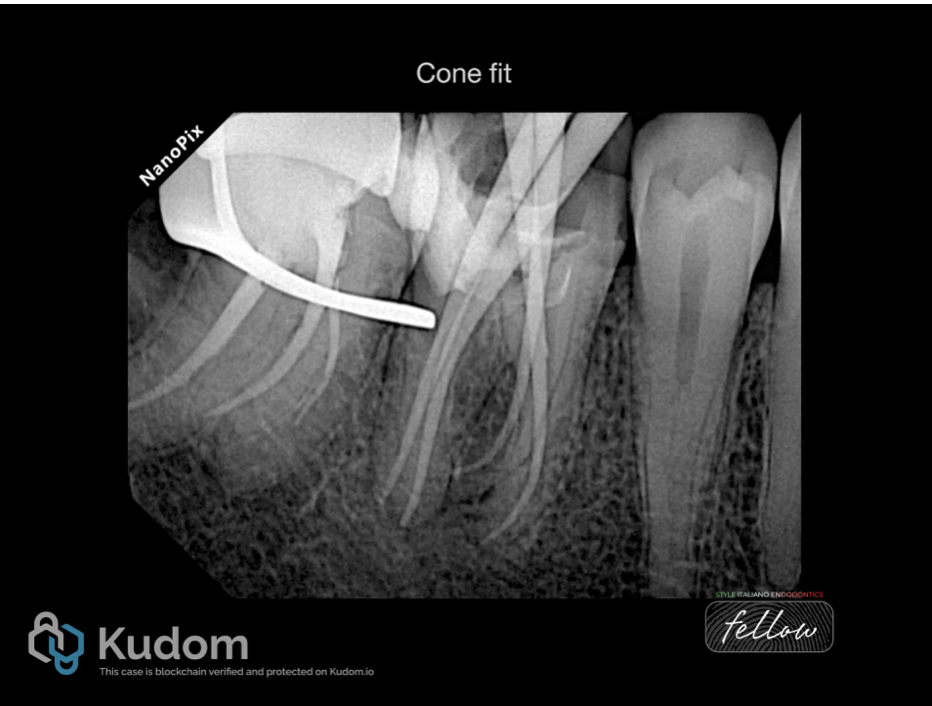

Fig. 6

After removing the old root canal filling and ledge bypass in the (RP) , A proper shaping and cleaning performed and cone fit x-ray image taken.